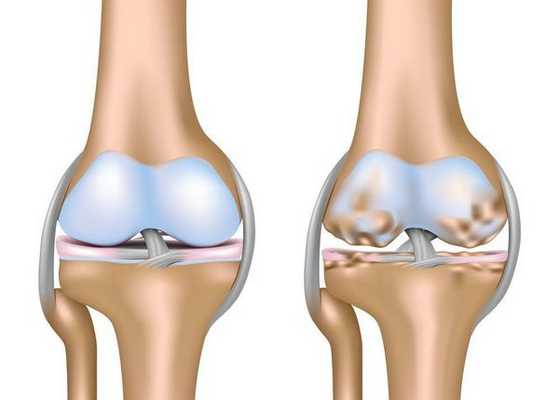

Артроз коленного сустава (гонартроз) — это прогрессирующее хроническое заболевание коленных суставов с повреждением, истончением и разрушением его хрящевой части (суставные поверхности бедренной и большеберцовой костей), а также поражением субхондральной кости. [2] [5] [16] Доказано исследованиями (артроскопия и МРТ), что помимо поражения суставного хряща в процесс вовлекаются мениски и синовиальная оболочка. Гонартроз — одна из самых распространенных ортопедических патологий. [4] [6] [9] [22] Существуют его синонимы — остеоартроз (ОА), деформирующий артроз. Заболевание является важной социально-экономической проблемой, так как широко распространено и значительно ухудшает качество жизни больных из-за постоянного болевого синдрома и, кроме того, становится причиной высокой инвалидизации. [15] [27]

До середины восьмидесятых годов прошлого века не было унифицированного определения заболевания. Только к 1995 году комитетом по остеоартрозу Американского колледжа ревматологии заболевание было охарактеризовано как результат действия механического и биологического факторов, приводящих к дисбалансу между процессами деградации и синтеза внеклеточного матрикса суставного хряща. [11] [19] В итоге происходит его разволокнение и дегенерация, образуются трещины, остеосклероз и уплотнение кортикального слоя субхондральной кости, растут остеофиты и формируются субхондральные кисты. [12] [29]

При артрозе (остеоартрозе) кроме прогрессивного разрушения хряща, потери его эластичности и амортизирующих свойств, в процесс постепенно вовлекаются кости. [7] [29] Под нагрузкой возникают заострения по краям (экзостозы), которые по ошибке считают "отложениями солей" — при классическом артрозе никакого отложения солей не происходит. Прогрессируя, артроз продолжает «съедать» хрящ. Затем деформируется кость, там происходит образование кист, поражаются все структуры сустава, и нога искривляется. [11] [17]

Гонартроз, II стадия

На второй стадии хрящевая прослойка резко истончается, а местами и вовсе отсутствует. [22] Появляются остеофиты по краям суставных поверхностей. Изменяются качественные и количественные характеристики синовиальной жидкости сустава — она становится гуще, более вязкой, что приводит к ухудшению питающих и смазывающих свойств. [14] [16] Боли более продолжительные и интенсивные, часто при движении появляется хруст. Отмечается незначительное или умеренное ограничение движений и небольшая деформация сустава. Прием анальгетиков помогает снять болевой синдром.

Гонартроз, III стадия

Отсутствие хряща на большинстве поражённых участков, выраженный склероз (уплотнение) кости, множество остеофитов и резкое сужение или отсутствие суставной щели. [8] [15] Боли практически постоянные, походка нарушена. Подвижность резко ограничена, заметна деформация сустава. Препараты НПВС, физиопроцедуры и другие стандартные методы лечения артроза коленного сустава неэффективны. [11]